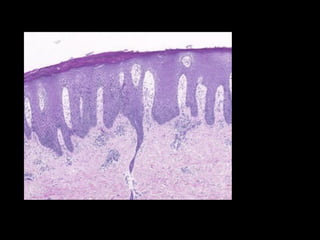

Psoriasiform   Lesions

Epidermal hyperplasia

Elongation of rete ridges

Histopathology